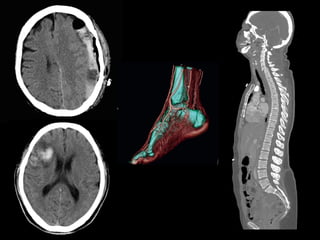

Imagens de radiografias

TOMOGRAFIA COMPUTADORIZADA

APARELHO DE RESONÂNCIA MAGNÉTICA

Imagem ponderada em T1

Imagem ponderada em T2

Contraste paramagnético